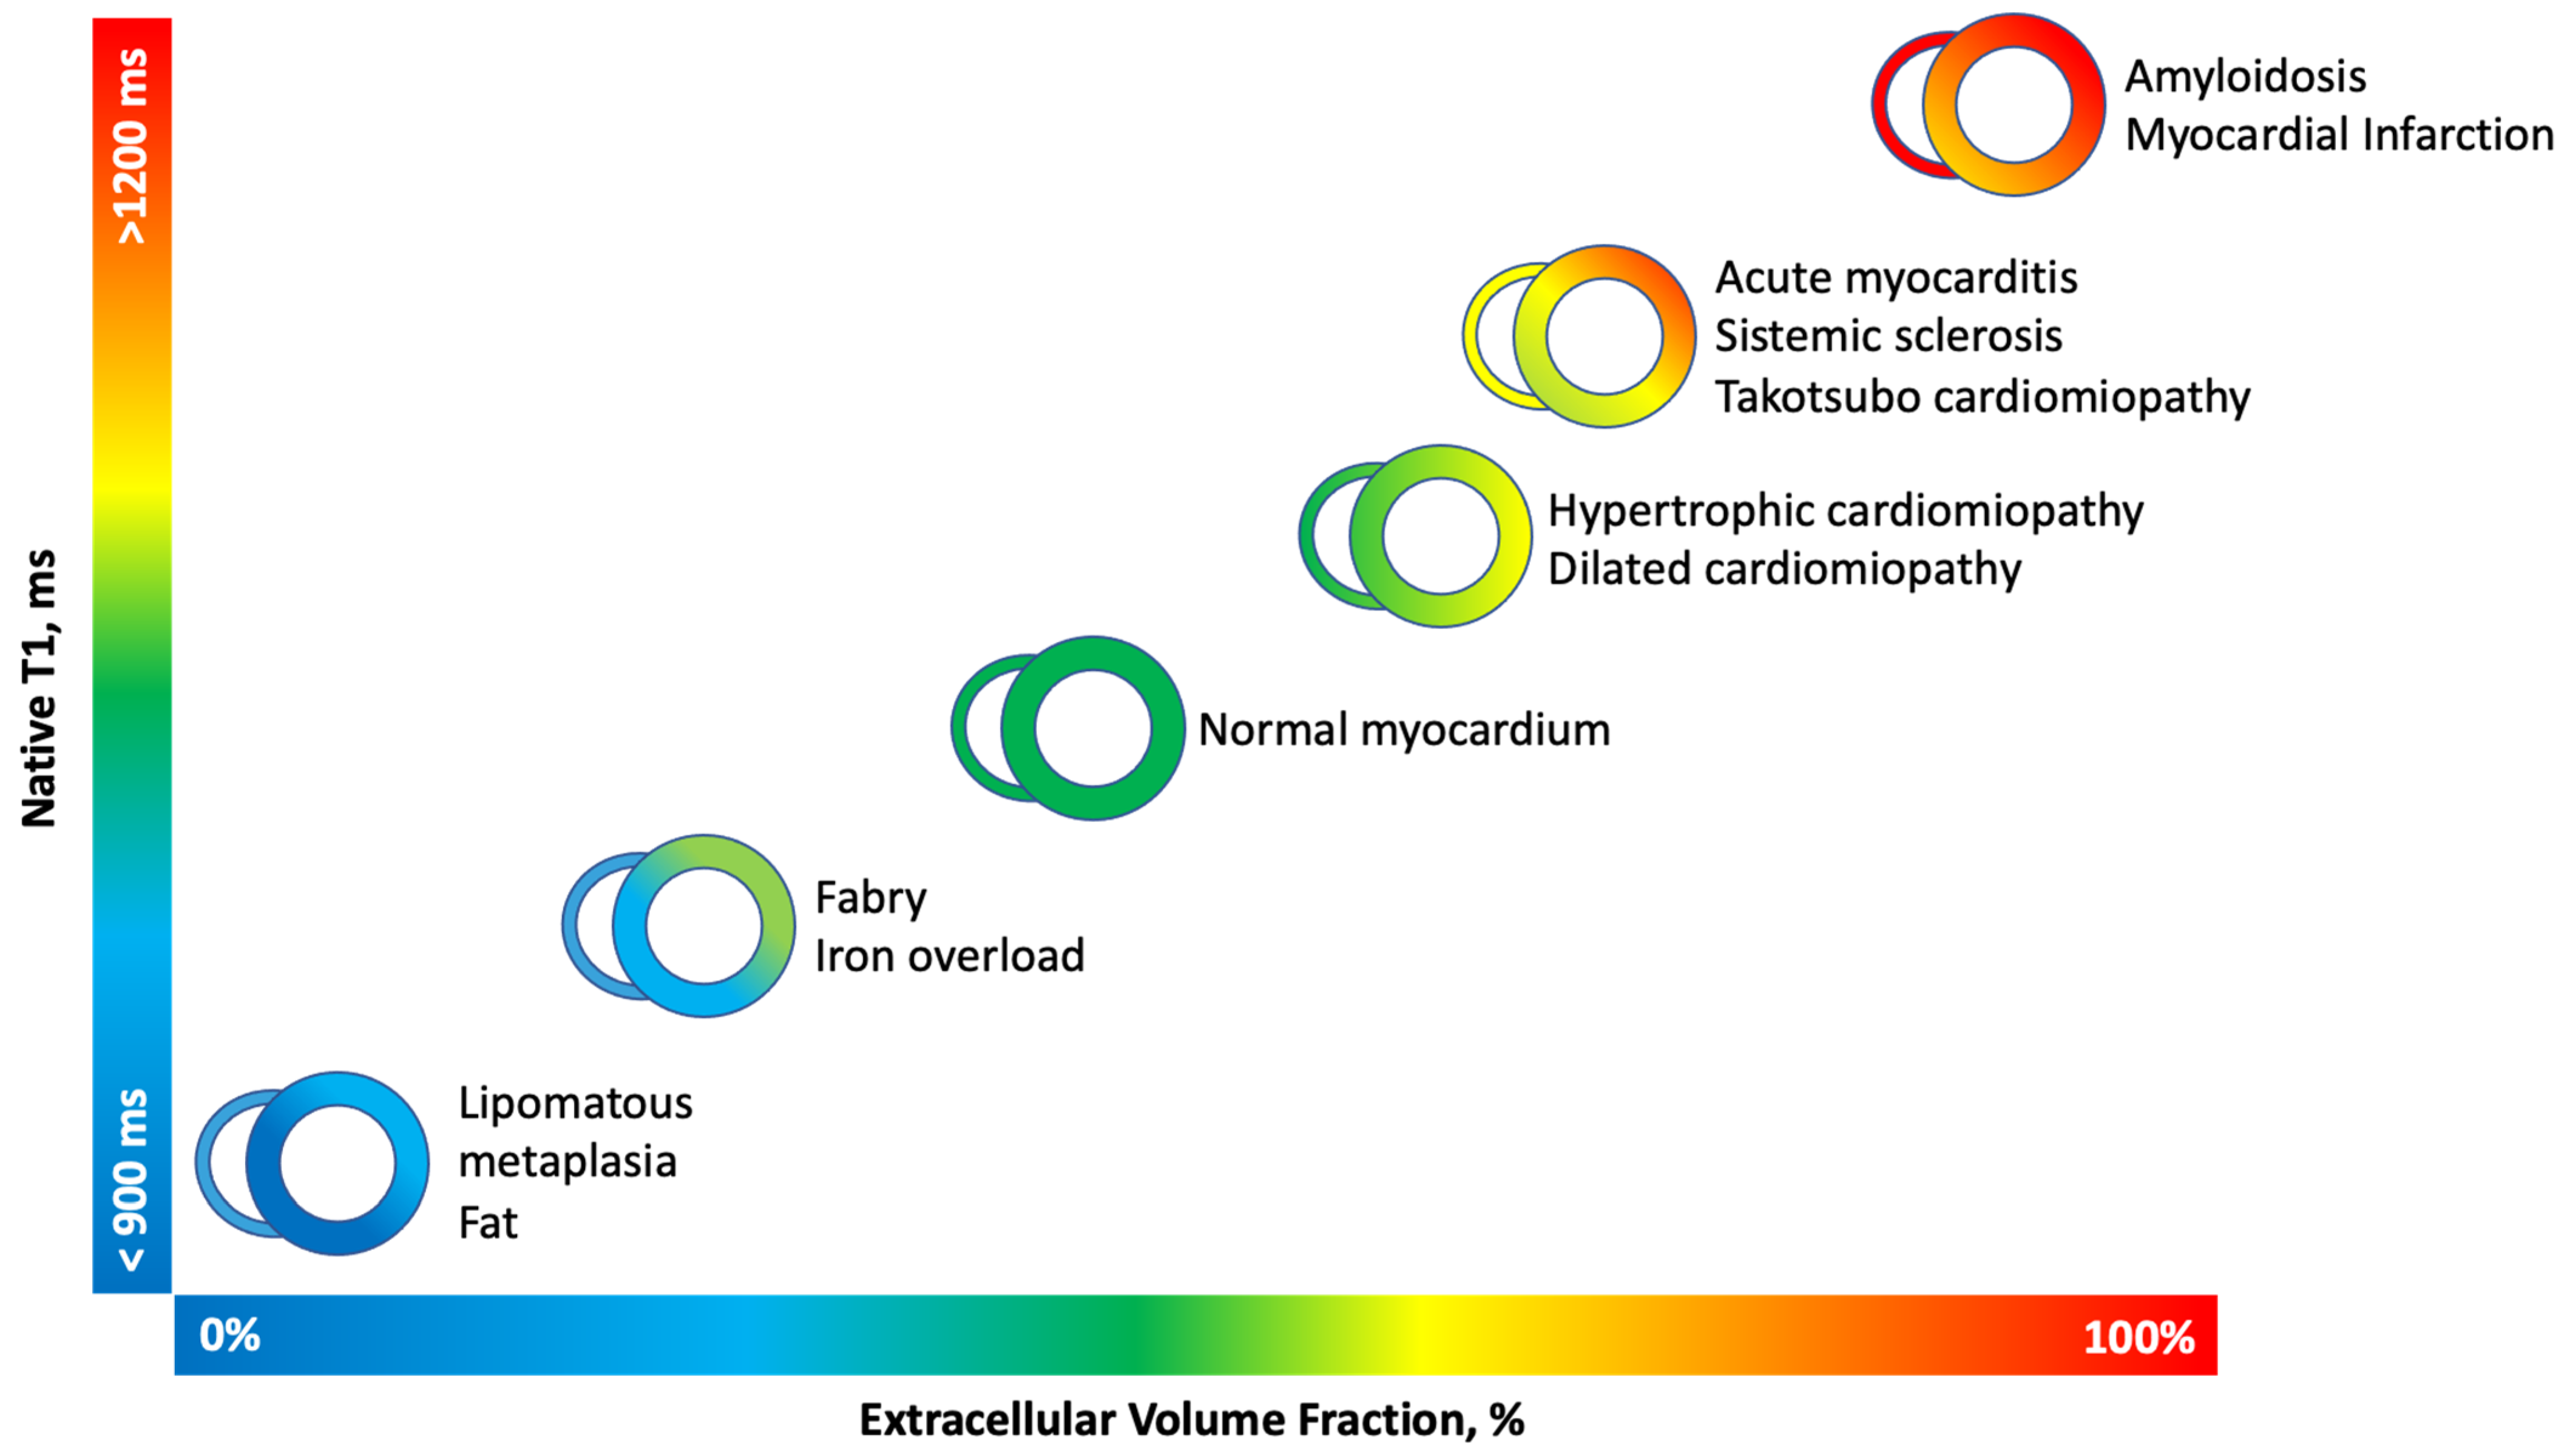

2. Physical Principles

3. T1 and T2 Mapping Imaging

3.1. T1 Mapping